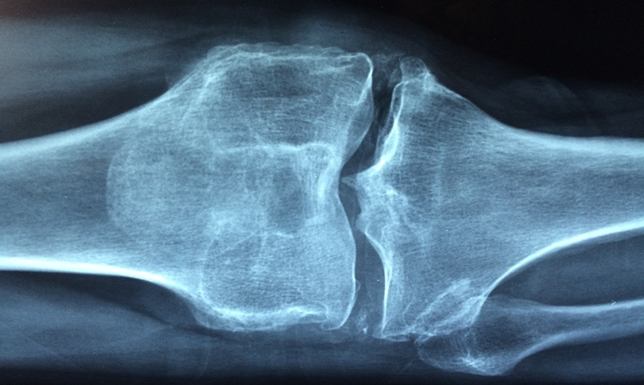

W czerwcu 2019 roku Szpital Wojewódzki im. dr. Ludwika Rydygiera w Suwałkach rozpoczął realizację projektu pn. „Modelowy program opieki zdrowotnej walki z osteoporozą w obszarze przygranicza polsko-białoruskiego” współfinansowanego ze środków Unii Europejskiej w ramach Programu Współpracy Transgranicznej EIS Polska-Białoruś-Ukraina 2014-2020. Projekt stanowi inicjatywę partnerską z Grodzieńskim Klinicznym Szpitalem Ratunkowym, której celem głównym jest poprawa jakości opieki zdrowotnej w zakresie ortopedii oraz reumatologii, ze szczególnym uwzględnieniem osteoporozy.

W ramach dwuletniego projektu zaplanowano szereg działań składających się na kompleksowy program walki z osteoporozą w obszarze przygranicza polsko-białoruskiego, w tym m.in.: modernizację infrastruktury szpitalnej, doposażenie szpitalnych oddziałów w nowoczesny sprzęt i aparaturę medyczną, szkolenia dla personelu medycznego, kampanię informacyjną oraz działania profilaktyczne skierowane do mieszkańców.